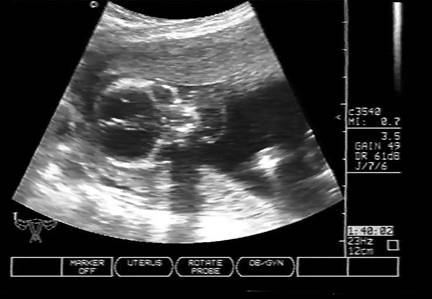

Fig . nr. 248. Chist de plex choroid , unilateral, la o sarcina de 17 sapt.